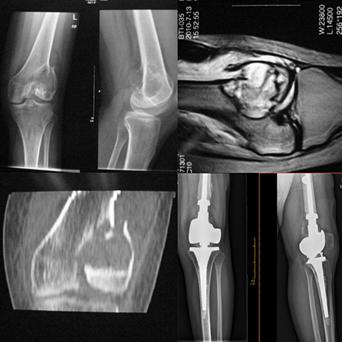

由于患者的病灶局限于股骨颈及股骨近端,专家决定为患者实施双动头人工股骨头肿瘤假体置换,而非全髋关节置换,这样做的意义是保留髋臼的软骨组织,因为软骨是骨肿瘤突破的天然屏障,保留软骨以阻断肿瘤细胞向髋臼侵犯。

骨肿瘤种类繁多,凡是发生在骨内或起源于各种骨组织成分的肿瘤,不论原发性、继发性还是转移性统称为骨肿瘤。

常见的良性骨肿瘤有骨样骨瘤、骨软骨瘤、软骨瘤等,原发性恶性骨肿瘤常见的有:骨肉瘤、软骨肉瘤、恶性纤维组织细胞瘤、尤因肉瘤、恶性淋巴瘤、骨髓瘤、脊索瘤等。

转移性骨肿瘤常见来源有:乳腺癌、前列腺癌、肺癌、甲状腺癌、肾癌。还有类肿瘤性的其他病损,包括骨囊肿、动脉瘤样骨囊肿、嗜酸性肉芽肿、骨纤维结构不良。其中青少年好发的恶性肿瘤最常见的是骨肉瘤、尤文肉瘤。

骨肿瘤疾病病因复杂,症状表现为:局部疼痛,局部肿块、功能障碍以及病理性骨折,恶性骨肿瘤晚期可能会出现恶病质等消耗性表现。对于骨肿瘤疾病,治疗以手术治疗以及多学科综合治疗为主,及时就医、早期发现尤为重要。

骨巨细胞瘤(Capamnacci III级)复发肿瘤假体置换术